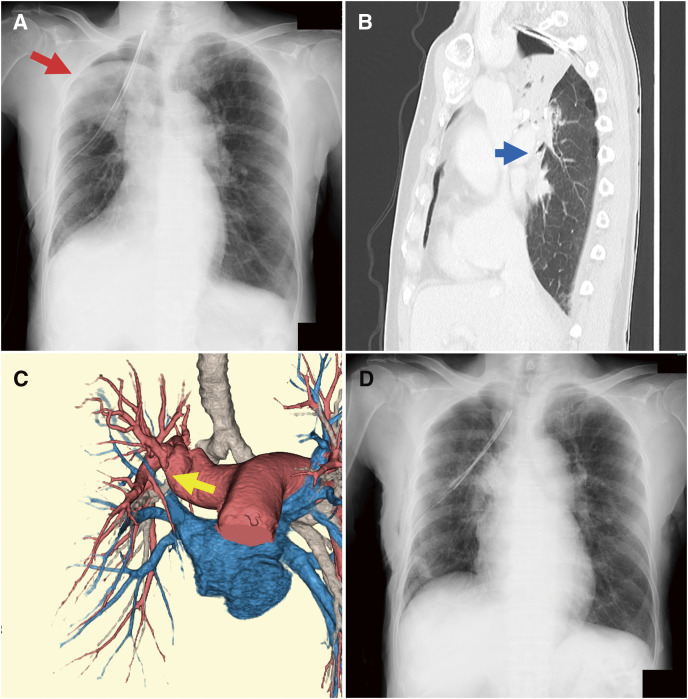

Purpose: Lung torsion is a rare postoperative complication of pulmonary resection caused by lobe displacement. This condition leads to bronchial or pulmonary vascular kinking, which results in airway obstruction or blood flow impairment. In particular, middle lobe torsion is commonly observed after right upper lobectomy. However, the conditions under which it occurs remain unclear. This study aimed to identify the risk factors for middle lobe torsion following right upper lobectomy.

Methods: From November 2012 to December 2024, 127 patients underwent thoracoscopic right upper lobectomy at our institution. Four patients diagnosed with postoperative middle lobe torsion were classified into the torsion group. These patients were retrospectively compared with those without torsion.

Results: Simultaneous partial middle lobe resection and the number of staples used for interlobar fissure formation between the upper and middle lobes were significantly associated with lung torsion. The cutoff value for the number of staples used in the upper-middle fissure formation was 4, demonstrating fair accuracy.

Conclusions: The risk factors for middle lobe torsion after thoracoscopic right upper lobectomy were simultaneous partial resection of the middle lobe and the number of staples used for interlobar fissure formation between the upper and middle lobes.